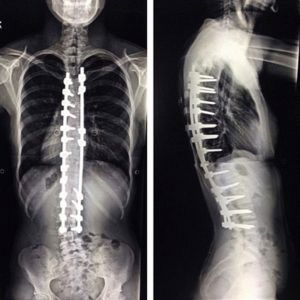

- прогрессирующее искривление позвоночника;

- стойкие нарушения работы внутренних органов, вызванные серьезным искривлением позвоночника (сколиоз, кифоз);

- артродез – хирургическая процедура при переломе позвоночника, включающая установку металлических конструкций для выравнивания и поддержки позвоночного столба;